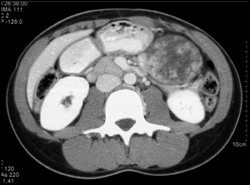

Lipoma in Head of Pancreas